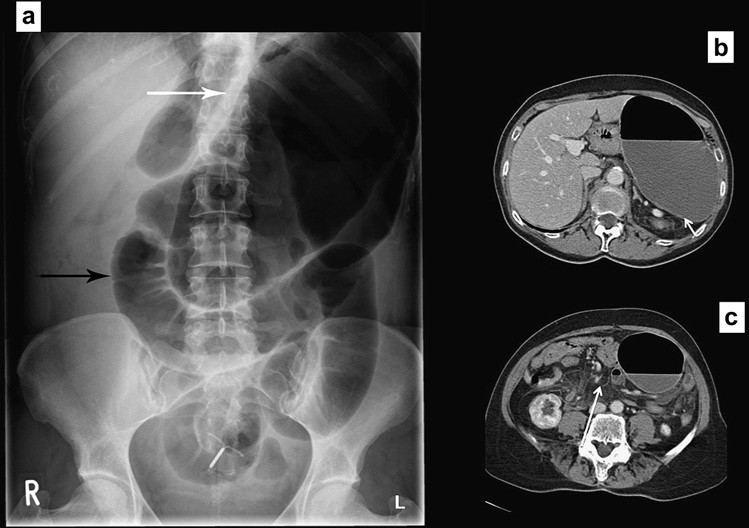

Mặc dù có mức biến đổi rộng về phân bố khí của ruột, nhất là do thành phần dịch trong ruột non biến đổi, sự di lệch hoặc phân bố không điển hình của khí (trong các quai) ruột có thể gợi ý bệnh lý mô trong ổ bụng. Sự di lệch khí ruột do tạng to lên hoặc khối trong ổ bụng, như nang buồng trứng to hoặc khối u thận (Hình 11 và 12). Mặc dù phim X quang không được chỉ định để phát hiện sự di lệch khí ruột khi nghi ngờ tạng to hoặc khối u ổ bụng, dấu hiệu di lệch được phát hiện khi tìm kiếm các triệu chứng khác của ổ bụng.

Hình 12. Di lệch các quai ruột (a) Một khối lớn từ tiểu khung đẩy các quai ruột lên phần trên của ổ bụng. (b) CT xác định khối u nang rất lớn của buồng trứng (c, d) Gan, lách to đẩy các quai ruột xuống phần dưới của ổ bụng.

Cổ chướng

Sự hiện diện một lượng dịch lớn trong ổ bụng gây di lệch và các quai ruột tập trung lại hoặc “bập bềnh” ở giữa ổ bụng. Hình ảnh này tạo nên mẫu hình cổ điển trên phim X quang bụng (lưu ý: chụp X quang bụng ở phương Tây gồm 2 phim X quang bụng tư thế nằm ngửa và ngực đứng hoặc ngồi). Trước tình trạng cổ chướng, thường siêu âm và chụp cắt lớp vi tính được yêu cầu để xác định nguyên nhân, thường là bệnh lý gan hoặc ác tính (Hình 13).

Hình 13. Di lệch các quai ruột (a) Các quai ruột bị đẩy vào trung tâm, khẩu kính còn bình thường. (b) CT xác định rất nhiều dịch ổ bụng.